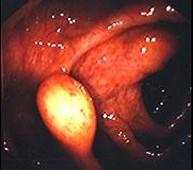

问题 女性,60岁,无临床症状,查体无明显异常,体检时的结肠镜检查图片(图1、2),2年后复查肠镜图片(图3、4),此患者最可能的诊断是 ( )

选项 A.Crhon病 B.大肠癌 C.脂肪瘤 D.大肠息肉 E.溃疡性结肠炎

答案 C